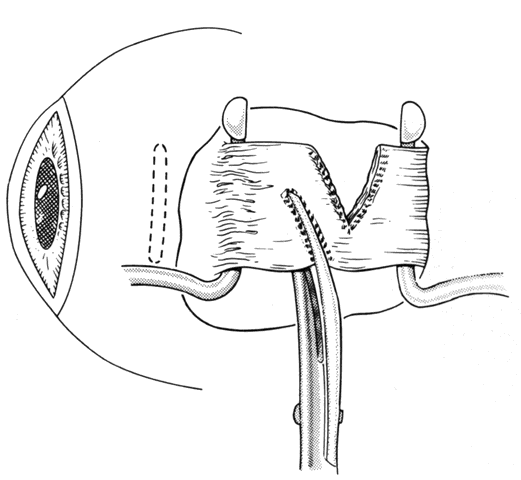

If a muscle tendon has been split during mobilization of the tendon or by passing a muscle hook under a scarred tendon, the marginal myotomy should be avoided. Placing cuts in the muscle may cause the muscle to be transsected (Figs. 37 through 40).

Fig. 37. When a muscle is split, a marginal myotomy is contraindicated.

Fig. 38. The split muscle is clamped.

Fig. 39. The cuts in the muscle divide it.

Fig. 40. The muscle can retract into the orbit.